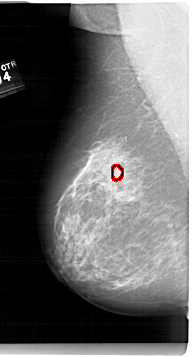

FILE: A_1679_1.LEFT_MLO.OVERLAY

TOTAL_ABNORMALITIES 1

ABNORMALITY 1

LESION_TYPE MASS SHAPE LOBULATED MARGINS OBSCURED-CIRCUMSCRIBED

ASSESSMENT 4

SUBTLETY 3

PATHOLOGY BENIGN

TOTAL_OUTLINES 1

BOUNDARY